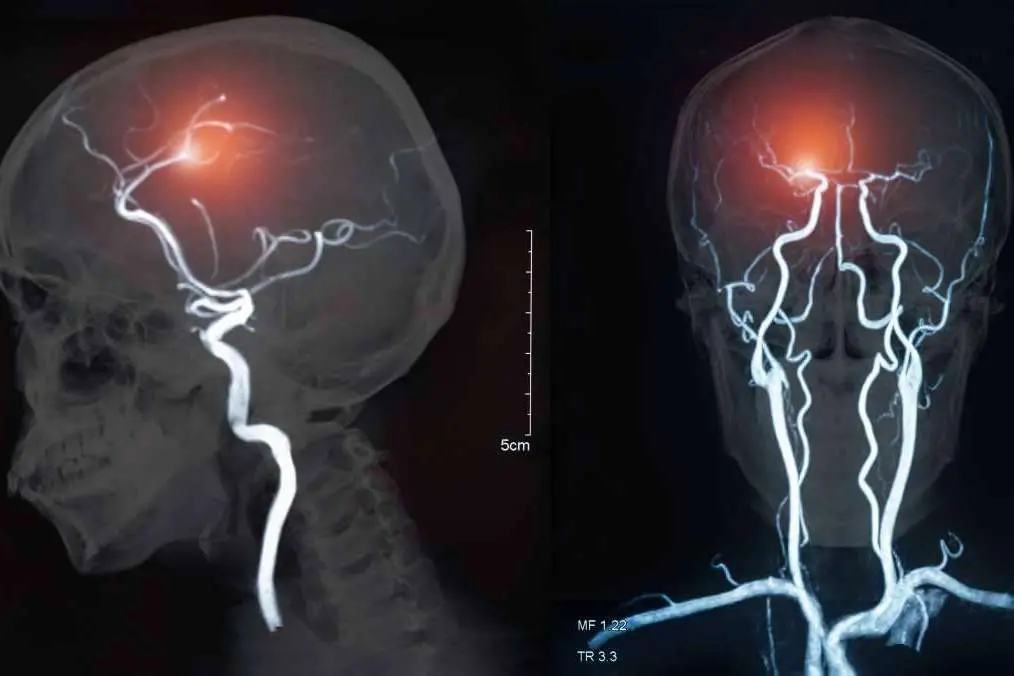

Dentro de estas últimas, el ictus es una de las que se presenta con mayor frecuencia, tomando en cuenta que cerca de 40 mil personas mueren por año a causa de la misma, según los registros de la Sociedad Española de Enfermedades Neurológicas.

A nivel nacional, las estadísticas confirman que unas 130 mil personas por año sufren un ictus. El mismo ocasiona diversos tipos de dificultades, que impiden que las actividades diarias puedan desarrollarse de manera normal

Teniendo esto en cuenta, el tratamiento de estimulación transcraneal profunda de tecnología BrainsWay que ofrece la Clínica Azorín es apto tanto para ictus isquémicos como ictus hemorrágicos, es decir, hemorragias generadas por la rotura de un vaso cerebral.